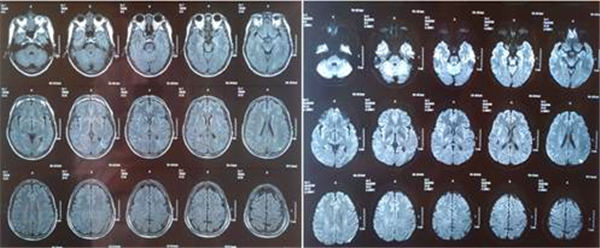

近日,闻先生又感到症状加重,并且发作频繁,再次到附近这家医院就诊,经头颅MRI显示:左侧基底节区及额顶叶新发脑梗死。

经头颅CTA显示:左侧颈内动脉起始部重度狭窄。